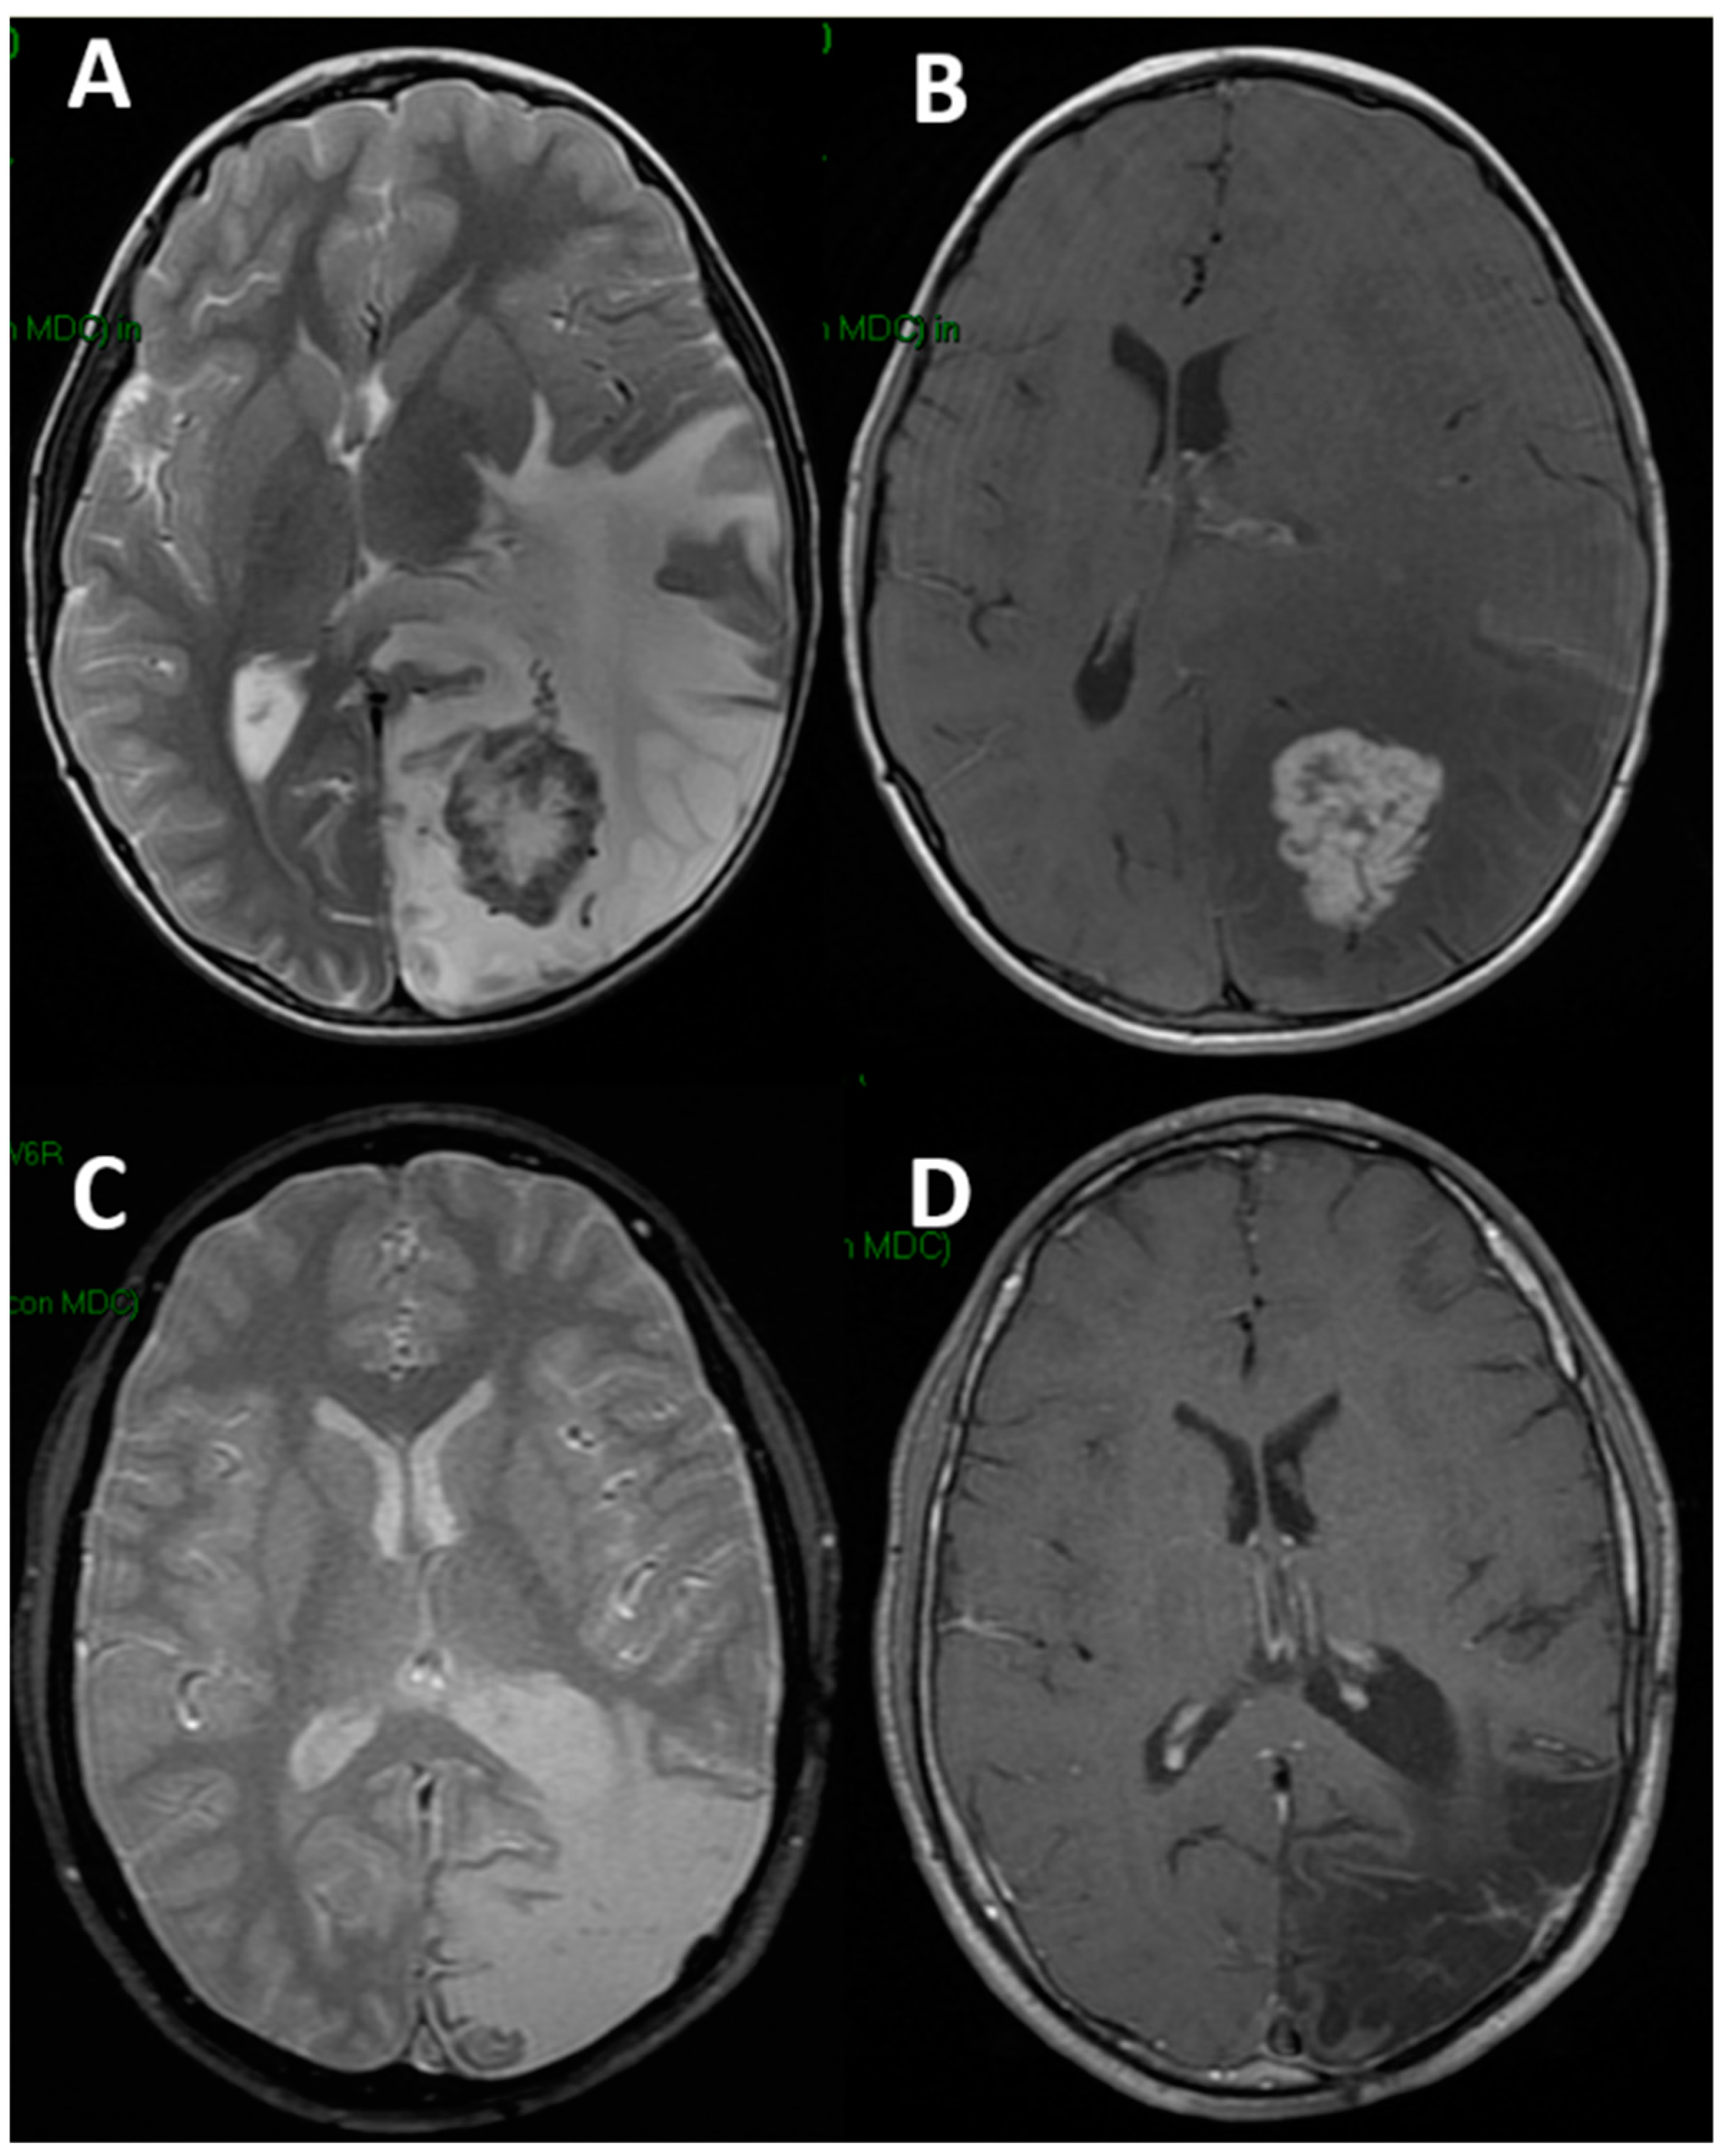

- Massimi, L.; Battaglia, D.; Bianchi, F.; Peraio, S.; Peppucci, E.; Di Rocco, C. Postoperative Epileptic Seizures in Children: Is the Brain Incision a Risk Factor? Neurosurgery 2018, 82, 465–472. [Google Scholar] [CrossRef] [PubMed]